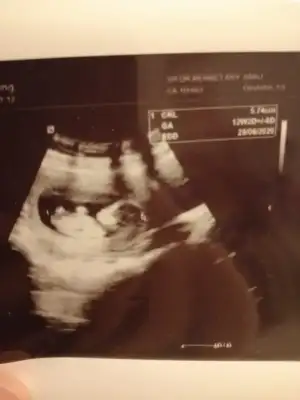

• IMG-20191218-WA0018.webp

IMG-20191218-WA0018.webp

15,9 KB · Görüntüleme: 100